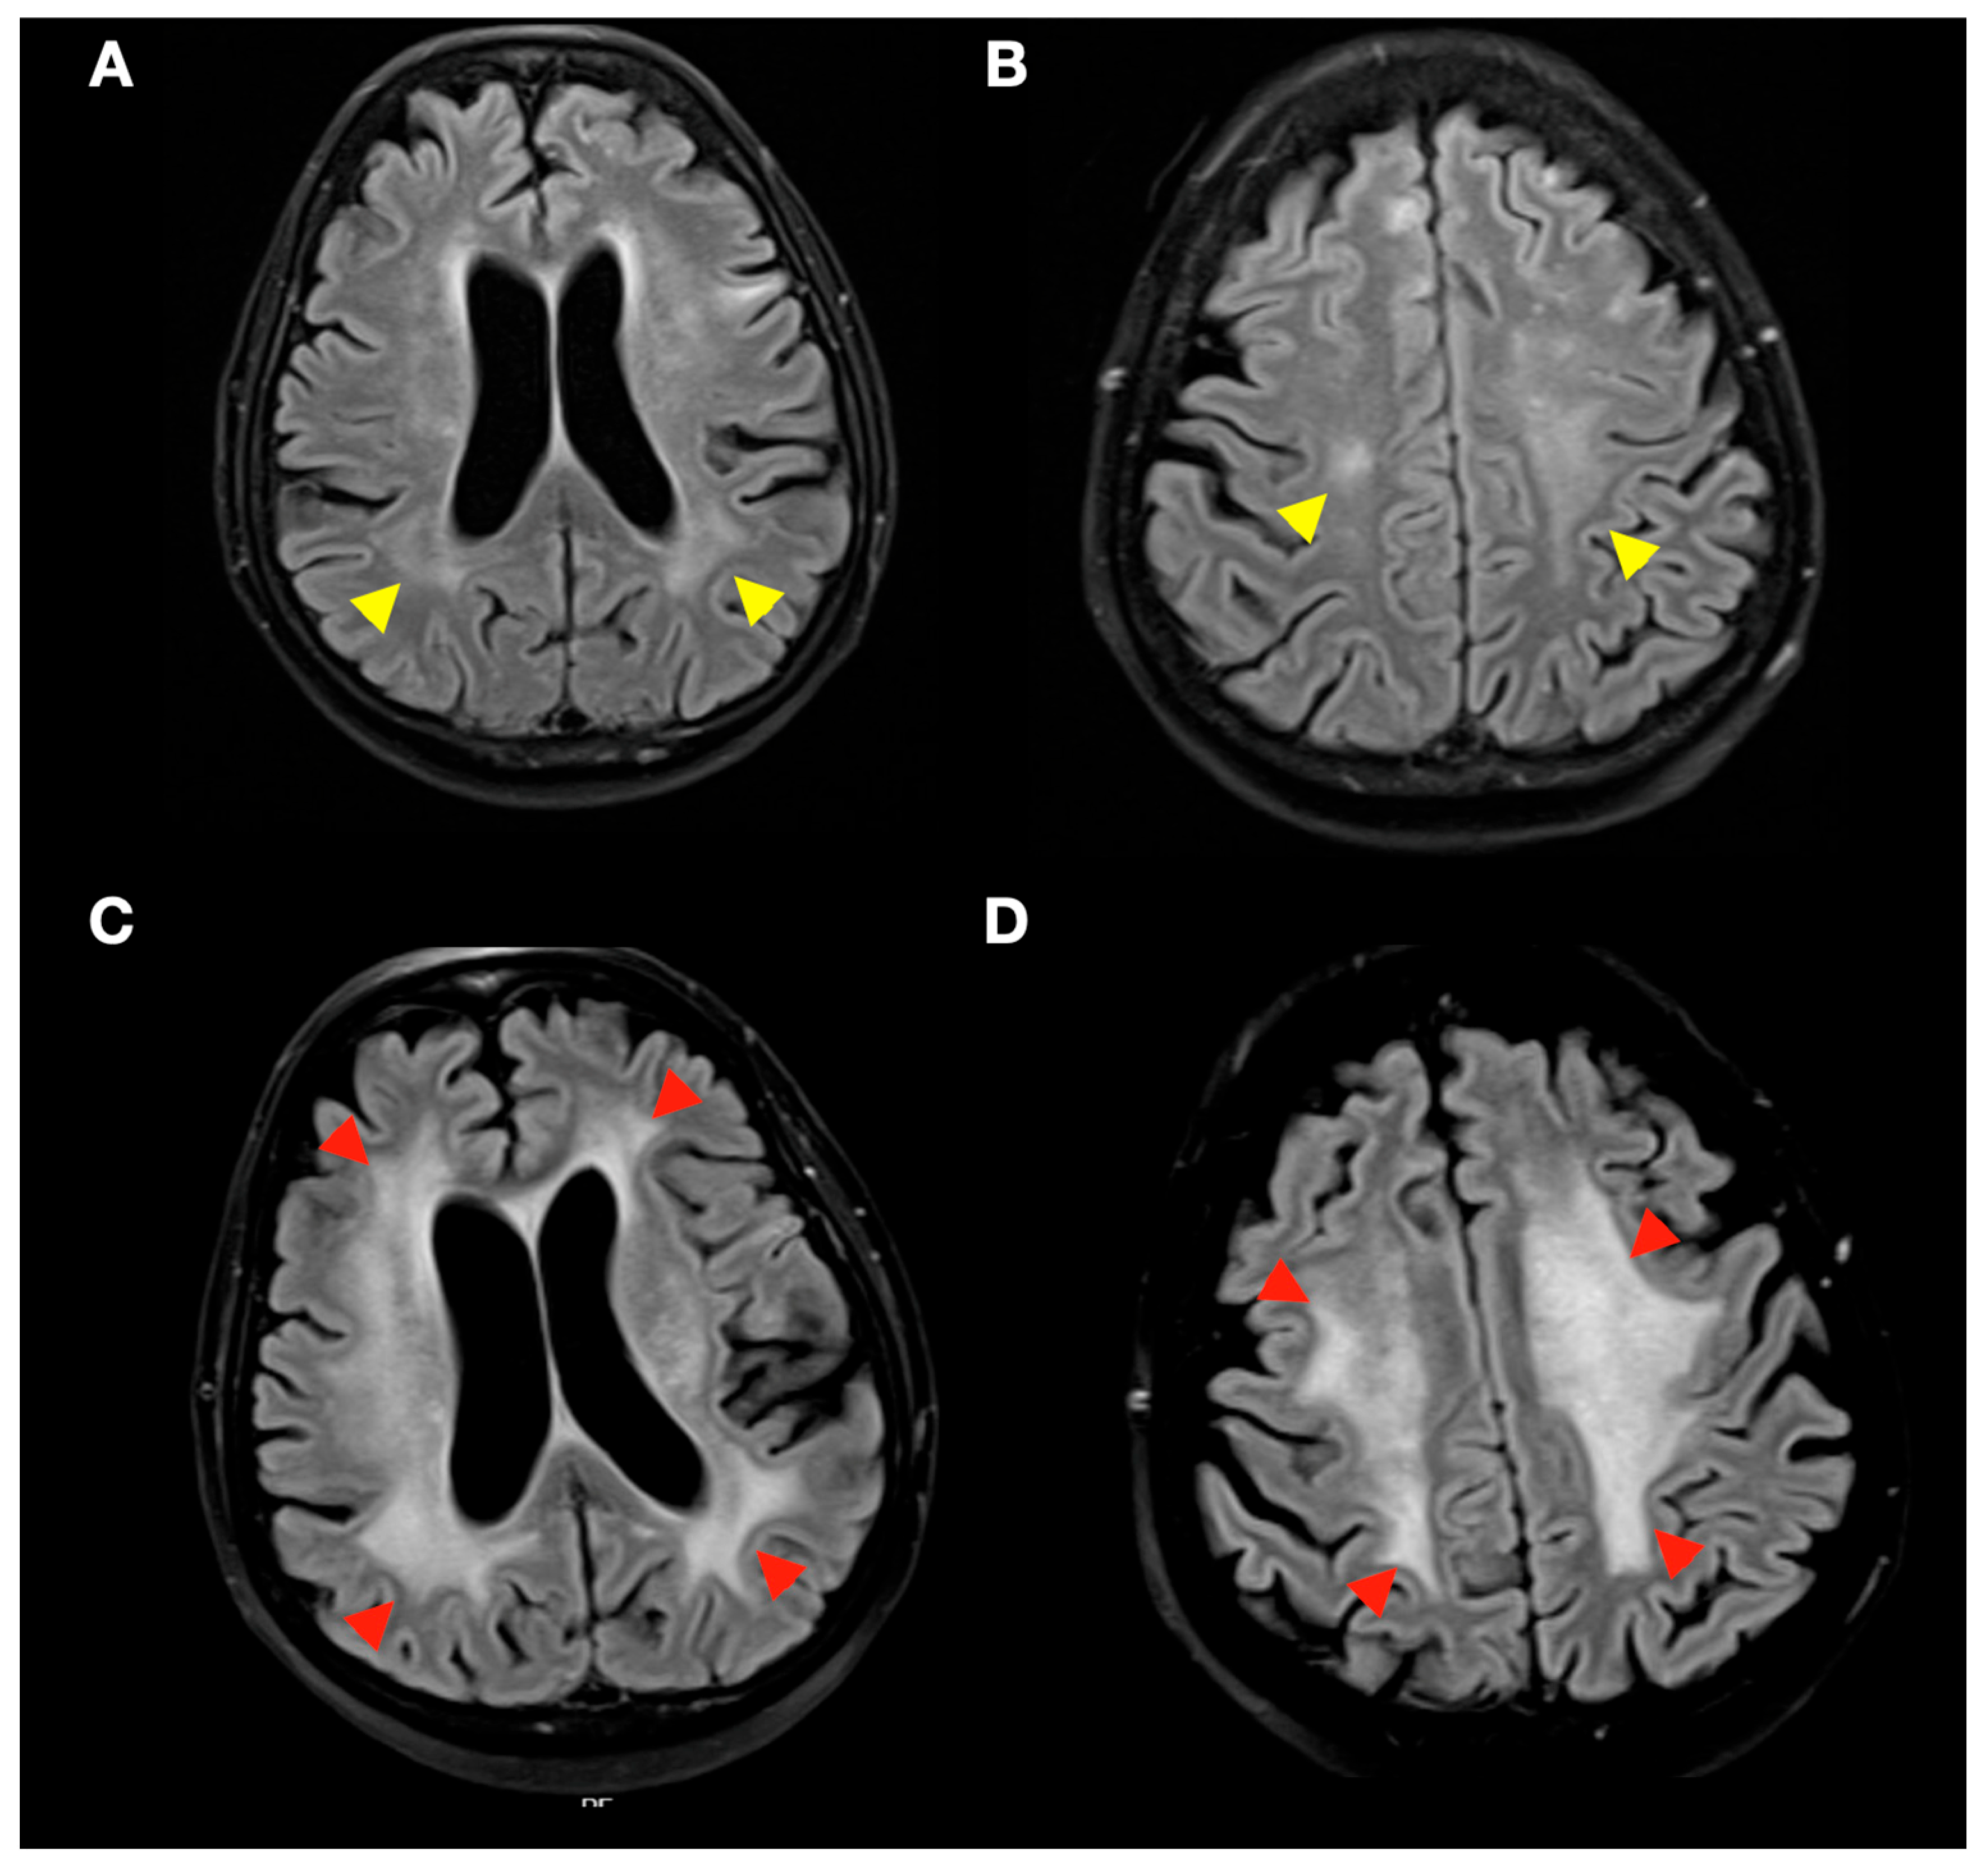

3.3. Radiological Complications of SRS Treatment